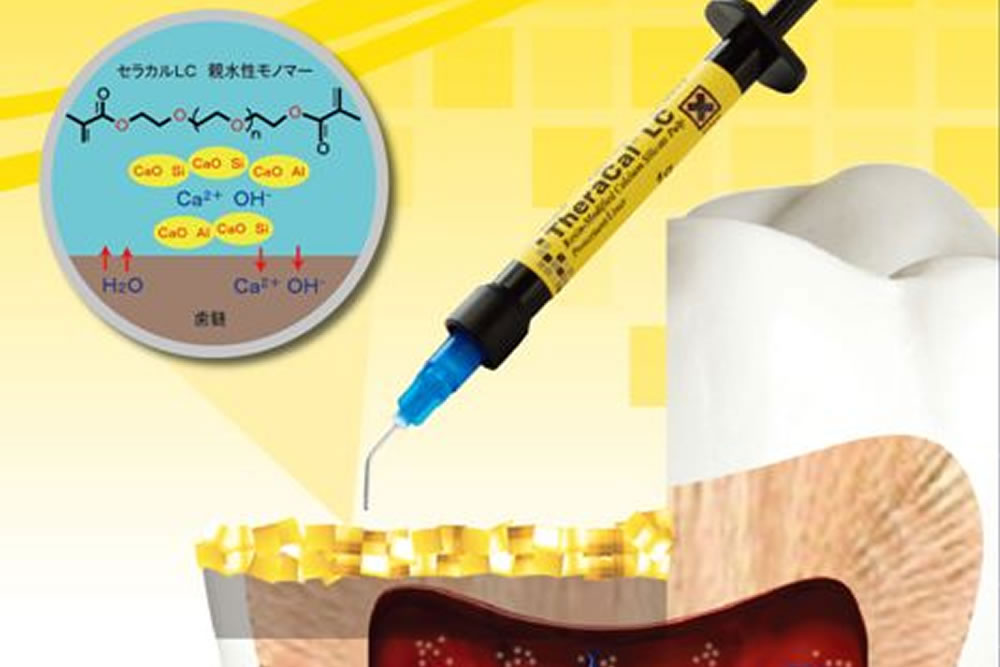

殺菌性と修復機能のMTAセメント

細菌物質を除去した後は、根管充填と呼ばれる根管内の空洞を埋める処置が必要となり、隙間なく埋める事で再発を抑える事ができるため、とても重要な処置となります。

細菌物質を除去した後は、根管充填と呼ばれる根管内の空洞を埋める処置が必要となり、隙間なく埋める事で再発を抑える事ができるため、とても重要な処置となります。

当院では、MTAと呼ばれる殺菌効果のある歯科用セメントで根管充填を行い、根管内部の徹底殺菌と緊密な封鎖を行っています。

根の中の消毒が終わったら、最終的な薬を詰めて根の中の空洞を封鎖する根管充填(こんかんじゅうてん)を実施。

MTAというセメントを根の中に詰めていきます。MTAセメントは殺菌したり、歯を再生させたり、穴の空いた歯の部分を埋めたりすることのできる新しい薬です。

MTAというセメントを根の中に詰めていきます。MTAセメントは殺菌したり、歯を再生させたり、穴の空いた歯の部分を埋めたりすることのできる新しい薬です。

通常、殺菌力の強い薬は歯や周りの組織に対しても悪い影響を与えますが、MTAセメントは体の組織に適度な刺激を与え、悪くなってしまった部分を再生させる作用があるお薬です。